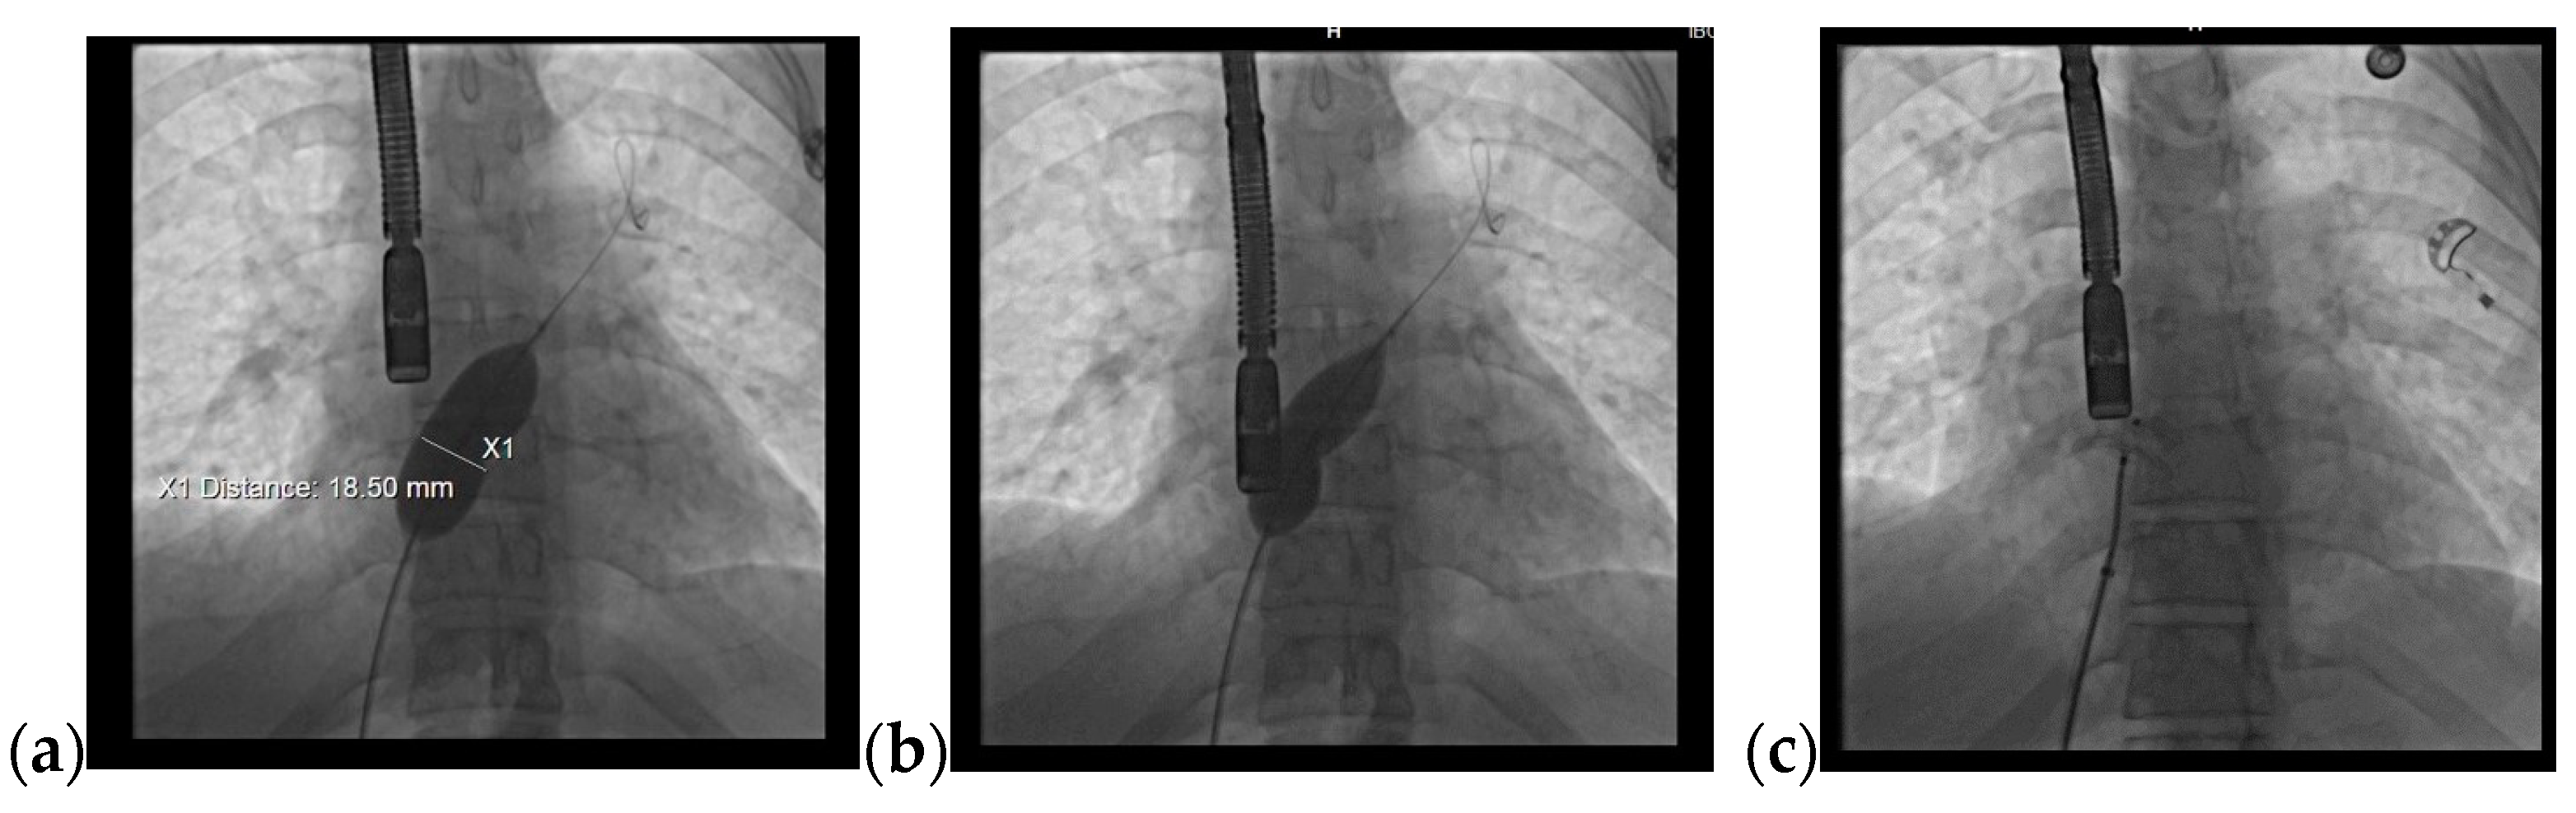

Considering the hemodynamic challenges of the RV and increased Qp/Qs ratio, the recommended treatment of the defect was based on transcatheter device closure (Figure 5a). In order to establish the perfect diameter of the closing device, the diameter of the defect can be measured by ultrasound, when 25% of the determined maximum value is added, or by fluoroscopy, when 2 mm are added. Subsequently, the ASD was percutaneously closed with an ASD® Amplatzer septal occluder prostheses 9-ASD-020 without any residual shunt or complications (Figure 5b,c).

Figure 5.

Transcatheter device closure: (a,b) Fluoroscopy, measurement of the defect with a diameter of 18.5 mm; (c) implant of a 20 mm Amplatzer device.